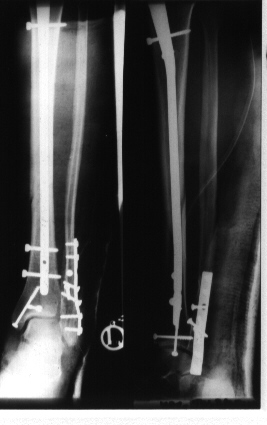

wamsstat.jpg (36192 Byte)Verriegelungsnagelosteosynthese beim Unterschenkelbruch

hier mit zusätzlichen Brüchen im Bereich des oberen Sprunggelenks